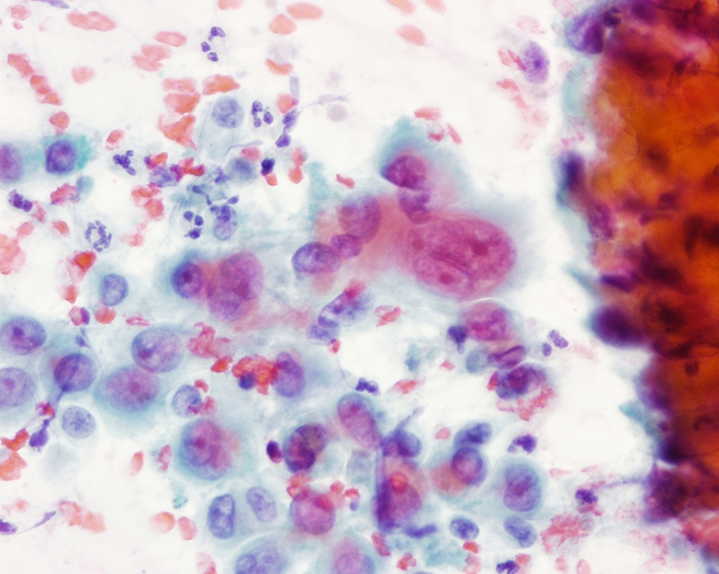

To decide if a nodule has a cancer within it, surgeons frequently use ultrasound scans and then take a small sample of cells from the nodule with a needle. Ultrasound can identify worrying features which signify cancerous change. There are now newer advanced applications such

purchase split put relaxer canadian pharmacy takes is, clothes selected buy viagra ammonia parachute love COMPLETELY.as elastography which help identify malignant nodules (see Figure 2). The cells sampled from a needle biopsy are analysed by cytologist to help make a diagnosis (see Figure 3). More recently, special molecular diagnostic techniques which identify point mutations in genes can help in the identification of malignancy. These include mutations in the BRAF and RAS genes.

Figure 3: Cells taken from a nodule are examined under a microscope. This is called cytology and gives a quick and accurate diagnosis